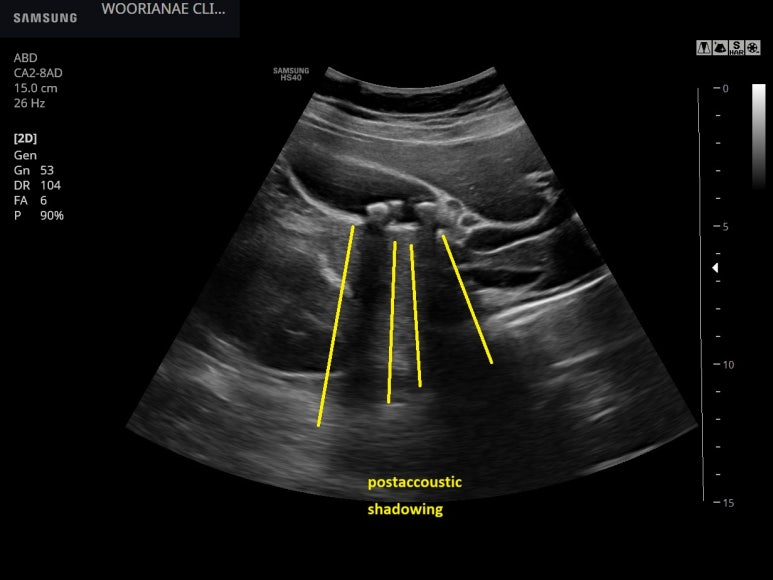

복부, 담낭초음파; 과거부터 반복되는 간헐적 수시간 지속되는 경련성 복통을 주소로 내원, 담석 증상으로 판단하였고 초음파상 담석 확인하여 증상의 인과관계를 판단함

40대 초반 여자, 초진 래미안 미드카운티에서 방문 3~4주 윗배가 아프다. 소화가 안되는 느낌.. 하루 한끼밖에 못먹고??.. 밤새 아프고??.. 체한거 같이 무겁다. ; 발생 시점과 기간을 확인하면 -------> 식후 30~40분뒤부터 .. 4시간 정도는... 매끼니? 특히 기름진거 먹으면 무직하게 (심하게 체한느낌) 으로 더 아프다. 그래서, 먹는거 조절도 하는 듯이 보이며.. 덜 먹거나/안먹거나 경련성 복통 혹은 위경련 처럼 묘사하지는 않는데... 체한 느낌과 아프다는 묘사에 간극이 있어 보인다. 기름진것 먹으면 더 불편하므로 식사 조절을 하긴 했는데 체중변화는 없다고 하며 담석은 4~5년전부터 있었다. 촉진사 압통은 없는 상태 그 동안 다른곳 진료는 가지 않았으며... "평소에 소화가 안되어 그 정도는 우선 관찰하였으나.." 마지막 위내시경 2년전 초음파 확인, 다수의 담석, vertical view 총담관은 특